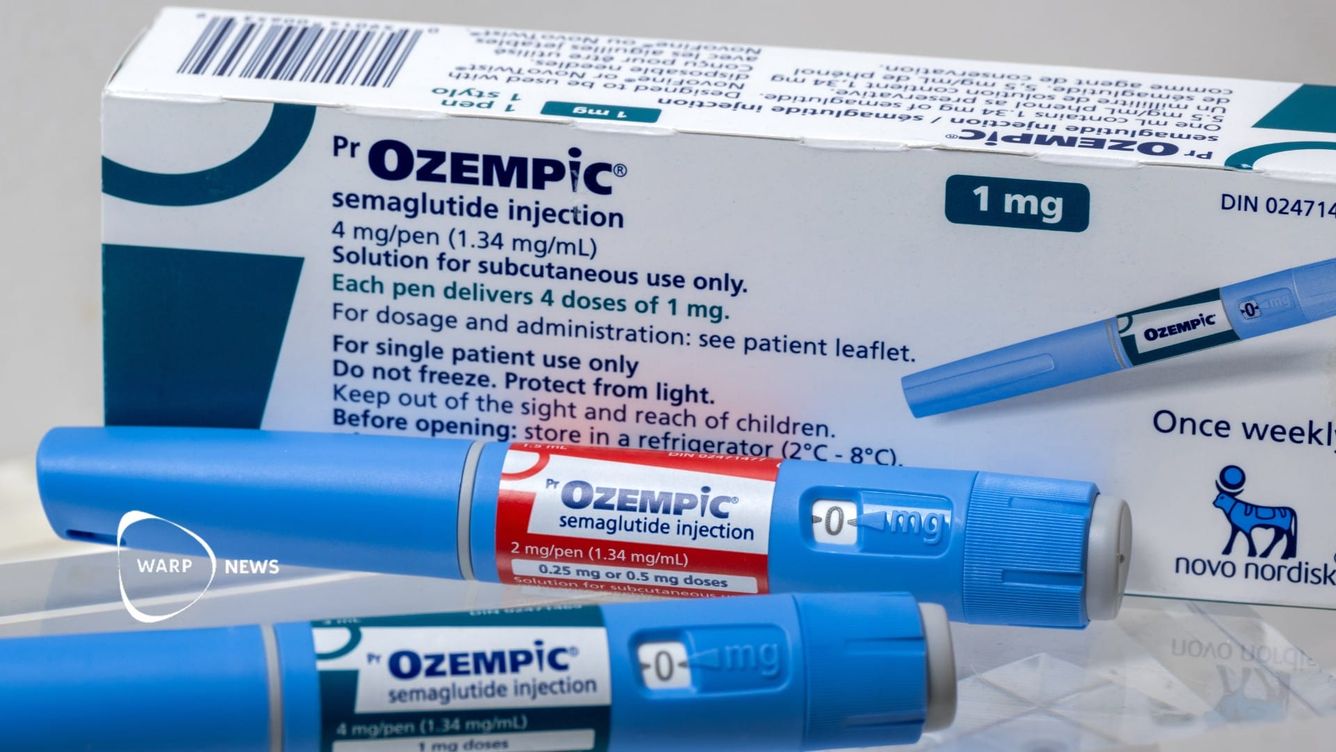

🏆 Årets vetenskapliga genombrott: Läkemedel mot fetma (och andra framstående upptäckter)

Fetma, en hälsokris som påverkar cirka 70% av vuxna i USA och mer än hälften i Europa, är kopplad till flera allvarliga sjukdomar. Nyligen har en ny klass av läkemedel, GLP-1 receptoragonister, ursprungligen för diabetes, visat stor potential i behandlingen av fetma med hanterbara biverkningar.